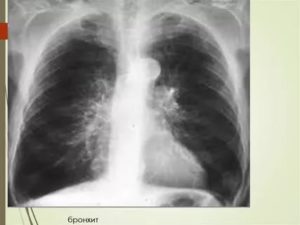

При хронической форме площадь поражения тканей значительно больше, чем при острой форме, поэтому на рентгеновском снимке проявления более заметны:

- прикорневые просветы легких оттенены узкими полосами сверху, рисунок которых напоминает трамвайные рельсы;

- при фиброзе тканей рисунок легких приобретает сетчатую структуру;

- повышается прозрачность фона легких — объем воздуха в альвеолах возрастает, а воздушная среда прозрачна для рентгена.